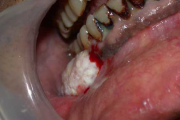

Mehaaniline trauma hambaharjaga